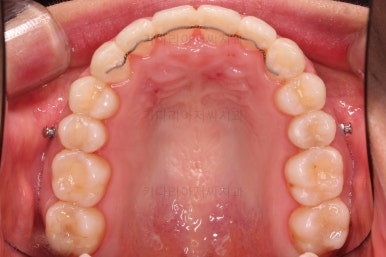

부산교정잘하는치과 초진 시 입안의 모습입ㄴ디ㅏ.

맞물림은 크게 나쁜 편은 아니었고요.

앞니 쪽이 위아래가 다 삐뚤고, 위에 작은 앞니 하나가 거꾸로 물리는 상태였습니다.

종료 시 사진입니다.

중앙선, 교합, 치아배열 모습 모두 양호해졌습니다.